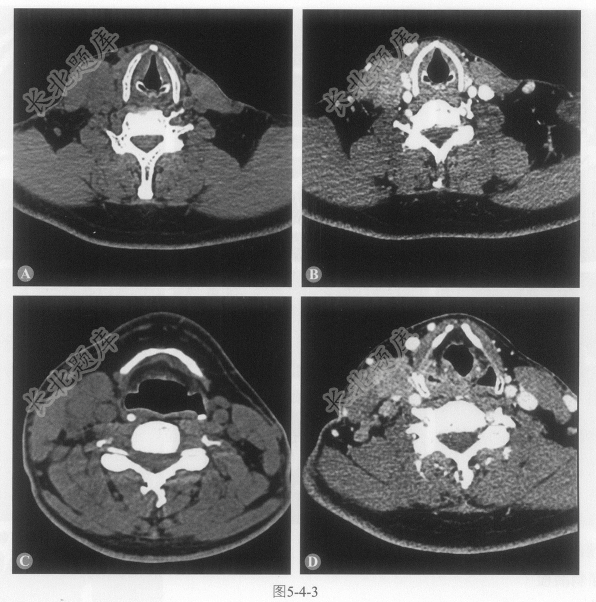

患者男性,46岁,慢性起病,主因发现右侧颈部肿物2年6个月入院。患者于入院前2年6个月发现右侧颈部肿物。查体示:右侧颈部胸锁乳突肌中1/3水平可触及肿物,质硬,与周围组织界限不清,大小约3cm×3cm×2cm(图5-4-3)。

A、右侧颈部Ⅱ、Ⅲ、Ⅳ、Ⅴ区多发肿大淋巴结

B、淋巴结部分融合

C、淋巴结于增强后可见明显均匀强化

D、淋巴结与右侧胸锁乳突肌分界不清

E、淋巴结边缘模糊不清